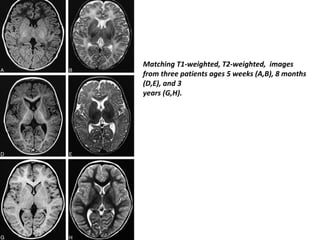

Matching T1-weighted, T2-weighted, images

from three patients ages 5 weeks (A,B), 8 months

(D,E), and 3

years (G,H).